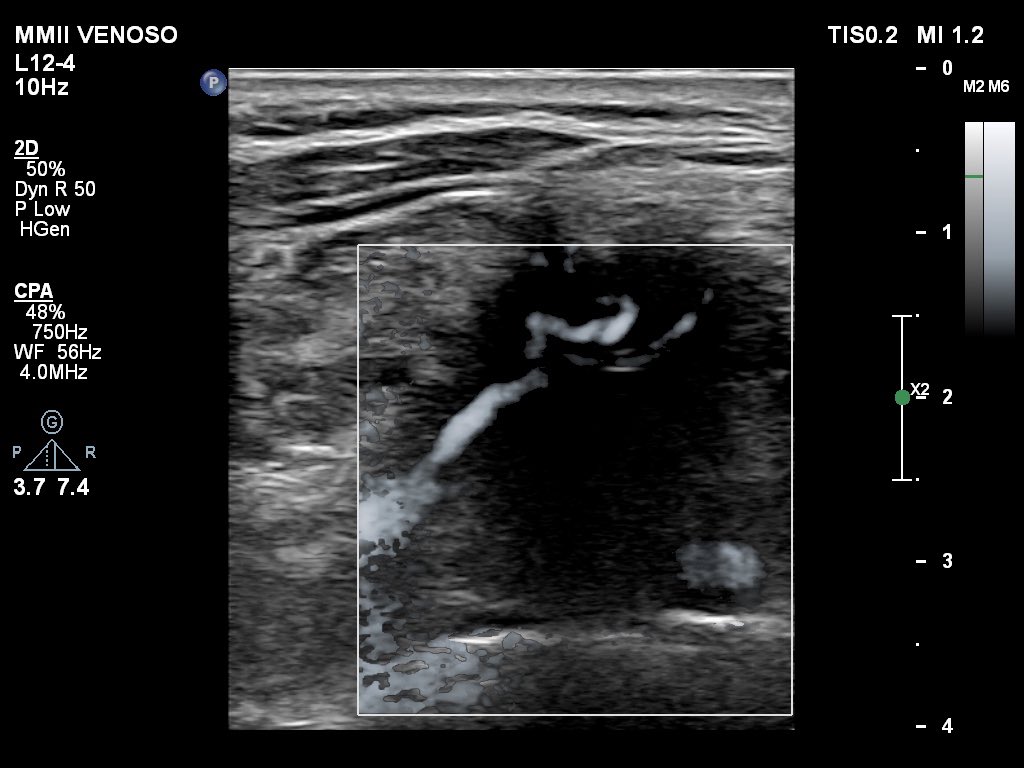

A great reference for lymph node assessment which helps standardized ultrasound terminology and measurements for lymph nodes. This provides clear guidance on describing size, shape, cortex, hilum, and vascularity.

obgyn.onlinelibrary.wiley.com/doi/10.1002/uo…